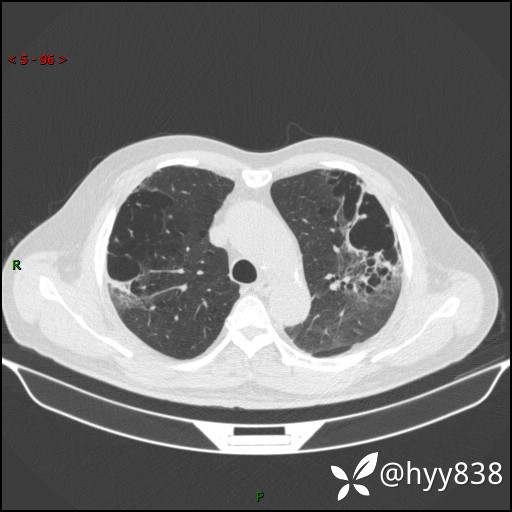

一周前胸部CT